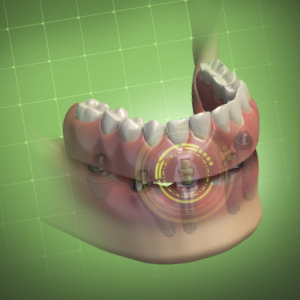

Dynamic Navigation for Dental Implants and Beyond—The Key to a Complete Digital Workflow

Robert W. Emery, BDS, DDS

Friday, March 29, 2024

This Compendium eBook offers a continuing education (CE) article that describes the various benefits and applications of dynamic navigation, and explains the workflows for implant surgery, including the workflow for full-arch reconstructions. Clinical examples are also provided in this arti...